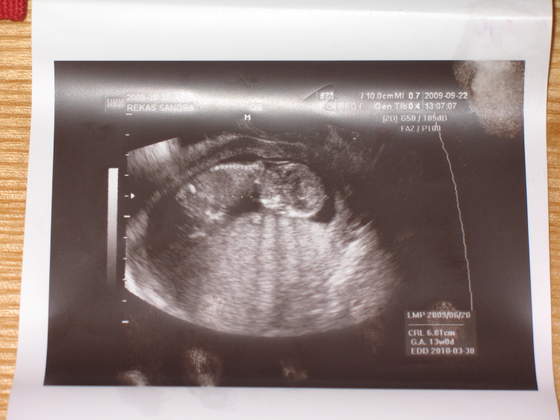

Tylko nie wiem czy to, co czuje to ruchy

Buziaczek dla kruszynki albo kruszynkaa to mój kruszynek)) albo kruszynka :-):-):-)

a to mój kruszynek)) albo kruszynka :-):-):-)